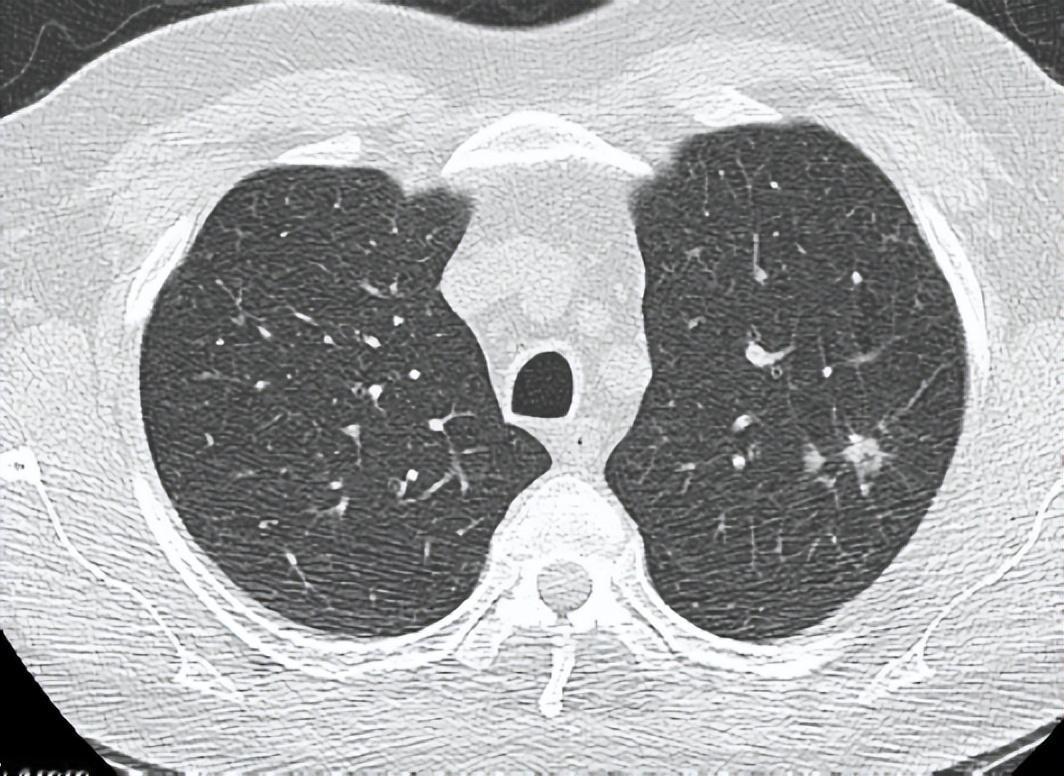

切结节为啥要 “连坐”?医生揭秘肺部手术的 “排雷” 逻辑 拿到肺部结节手术方案,很多患者都会懵:“明明结节只有芝麻大,为啥要切一大块肺?还要动淋巴结?” 其实这不是医生 “过度治疗”,而是给健康上双保险。作为呼吸科医生,我给大家打个比方:肺结节就像家里发现的一只 “可疑老鼠”,扩大切除不是 “滥杀无辜”,而是连窝端掉它的藏身地,所以即使是6mm的结节,有时候也要切除10cm的正常肺。 肺部结节哪怕很小,也可能有微转移的风险。扩大切除能确保切缘干净,避免残留肿瘤细胞 “死灰复燃”。而淋巴结就是身体的 “交通枢纽”,肿瘤细胞很可能顺着淋巴管 “溜” 到这里安营扎寨。 淋巴结清扫就是全面 “排雷”:一方面能判断肿瘤有没有转移、分期如何,为后续治疗指路;另一方面能直接清除潜在病灶,降低复发风险。 简单说,这是一套 “精准打击 + 全面防控” 的组合拳。看似多切了一点肺、多清了些淋巴结,实则是用最小的代价,换最长远的安心。毕竟,治肿瘤,防患于未然永远是上策!